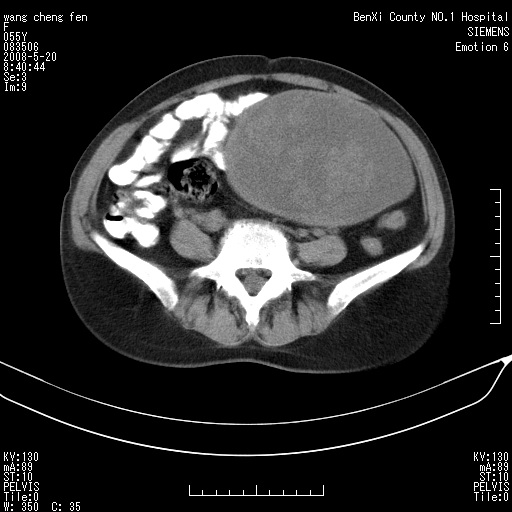

女、绝经后阴道流血3个月

左侧附件区可见一囊性占位,边缘清楚,内可见不规则形软组织影 ce:囊壁及内部可见强化 考虑 卵巢囊腺瘤

左侧附件区巨大囊实性病灶,边缘光整,病灶囊壁较厚,增强示囊壁及实性部分明显强化,强化呈度与宫体实质大致相同,宫腔积液征像,未见盆腔积液等其他异常,考虑左侧卵巢囊腺癌,不除外囊腺瘤及浆膜下肌瘤坏死

左侧附件区巨大囊实性病灶,边缘光整,病灶囊壁较厚,增强示囊壁及实性部分明显强化,强化呈度与宫体实质大致相同,宫腔积液征像,未见盆腔积液等其他异常。绝经后阴道流血3个月,结合病史左侧卵巢囊腺癌首先考虑,宫腔扩大不除外累及。期待结果。

支持浆膜下子宫肌瘤.之前由于网络原因未看全图片,现在重看,宫颈见一类圆形低密度影,增强轻度强化,低于肌层强化,宫腔扩大,考虑宫颈癌伴宫腔积液可能性大.

囊实性肿块分隔厚度较大,厚薄不均,增强实性成分明显强化,有不规则阴道流血,卵巢囊腺癌可能性大。

1,宫颈部占位,宫颈癌?2,左侧附件区囊实性占位,界较清,实质部分强化明显。考虑浆膜下或阔韧带肌瘤囊变可能大。囊腺类肿瘤不除外。